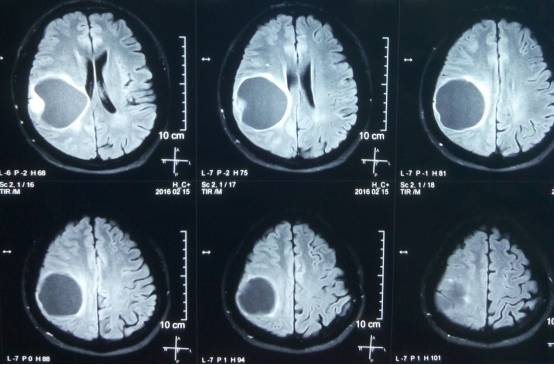

头颅MR示:右颞顶囊性占位伴结节,考虑胶质瘤可能。MRI T1为等信号(图1);T2囊液为高信号(图2);结节为均匀增强(图3);弥散相显示弥散受限(图4)。

图2. T2囊液为高信号。

术后患者恢复良好,神志清,精神佳,四肢肌力V级,肌张力正常,病理征(-)。术后CT(图5)MRI(图6)未见血肿,肿瘤全切。

图6. 术后48 小时 MRI (增强)。

PXA在CT平扫时表现为低密度囊性病变,境界多较清楚;附壁结节呈稍低密度或等密度,壁结节常紧邻软脑膜;囊性区因含有蛋白或出血,在CT上为略高于脑脊液的液性密度。在MRI上T1W1囊性区呈低信号,壁结节为低或等信号,T2W1为囊性区呈高信号,壁结节为稍高信号。增强扫描可见肿瘤附壁结节明显强化,囊壁可轻度强化或不强化,囊壁强化代表囊壁为肿瘤组织,囊壁不强化说明囊壁为反应性增生的胶质细胞构成。影像学典型表现为囊性病变伴壁结节,少数呈囊实性病变,钙化少见。充分认识这些影像特征有助于提高其诊断及鉴别诊断的准确性,为临床治疗及对预后的判断提供重要的参考价值。少数PXA表现不典型,呈囊实性病变,表现为密度或信号不均匀,增强扫描呈不均匀强化。